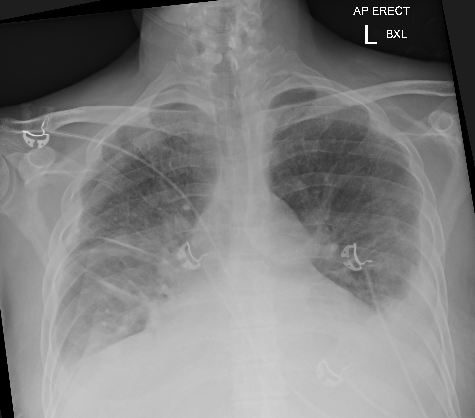

Chest XR and ECG are shown below, what do you think?

• CXR shows bilateral pleural effusions and marked bilateral pulmonary oedema. There is likely cardiomegaly (noting AP film)

• This is in keeping with severe pulmonary congestion.